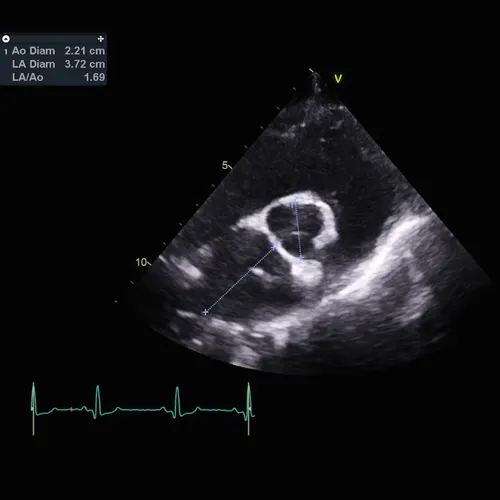

Figure 2 Measurement of the left atrial:aortic root ratio on a patient diagnosed with degenerative valve disease that would meet the criteria for left atrial enlargement according to the EPIC study criteria (ie, LA/Ao >1.6)

Dogs (n = 360) were enrolled in this study (Evaluation of Pimobendan In dogs with Cardiomegaly caused by preclinical mitral valve disease [EPIC]) to compare the effectiveness of pimobendan vs placebo in delaying onset of CHF signs, cardiac-related death, or euthanasia. Dogs (9.1-33.1 lb [4.1-15 kg] body weight) were admitted if they were diagnosed with MMVD based on the presence of a grade 3/6 or greater left apical systolic murmur, echocardiographic evidence of degenerative changes to the mitral valve apparatus, and presence of mitral regurgitation. They also had to have sufficient cardiomegaly meeting specific echocardiographic and radiographic parameters for left atrial and left ventricular dilatation (Figures 1 and 2).